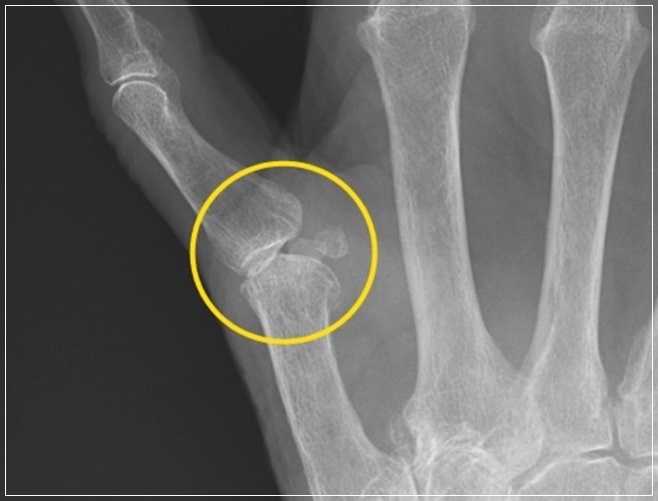

또한 나도 모르는 사이 손가락이 아파오거나 심지어 통증 때문에 손가락이 제대로 구부러지지 않는다면 방아쇠수지증후군을 의심해 봐야 한다. 손가락을 구부릴 때 `딸각` 소리가 나 방아쇠를 당기는 느낌과 비슷하다고 해 붙여진 이름으로 손가락 사이에 염증이 생겨 통증을 동반하게 되는 질병을 뜻합니다.